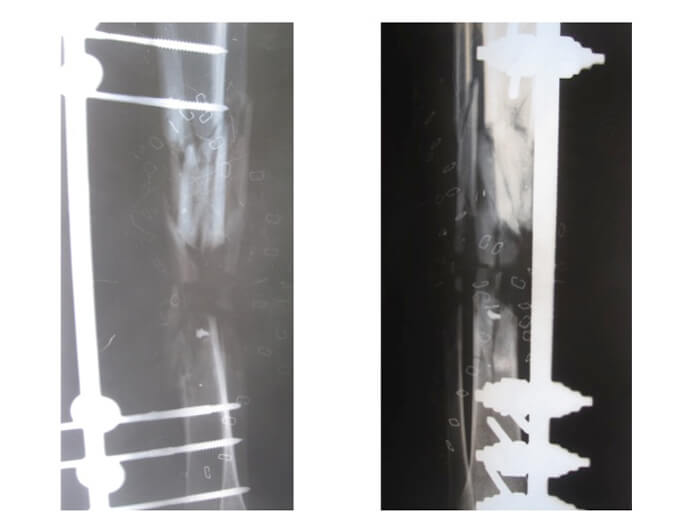

Figure 2a.

Figure 2b.

Figure 2c.

Figure 2a-c: Success story of patient treated by local surgeons: orthoplastic collaboration in country.

2a: 19-year-old male with a Gustilo IIIb middle 1/3rd tibia and fibular fracture, left leg

2b: Treated acutely with debridement and external fixator: x-ray at 2.5 months shows good alignment and signs of union.

2c: Fracture site was covered by a local fasciocutaneous flap within 11 days of the acute injury

Cases were screened and many had received timely orthoplastic care with excellent outcomes (Figure 2a-c). The local teams should be applauded that 70% of the open fractures received immediate, acute debridement and placement of an external fixator. The remaining 30%, with less serious open fractures, all received debridement and a fixator within three days of the injury. Forty percent of the fractures seen at screening needed no further orthopaedic intervention and 50% did not need plastic surgery interventions. Local education programmes clearly provide the best overseas aid possible. A UK teaching charity has supported local orthopaedic surgeons with training in limb reconstruction since 2009. This capacity building prior to this crisis saved many limbs.